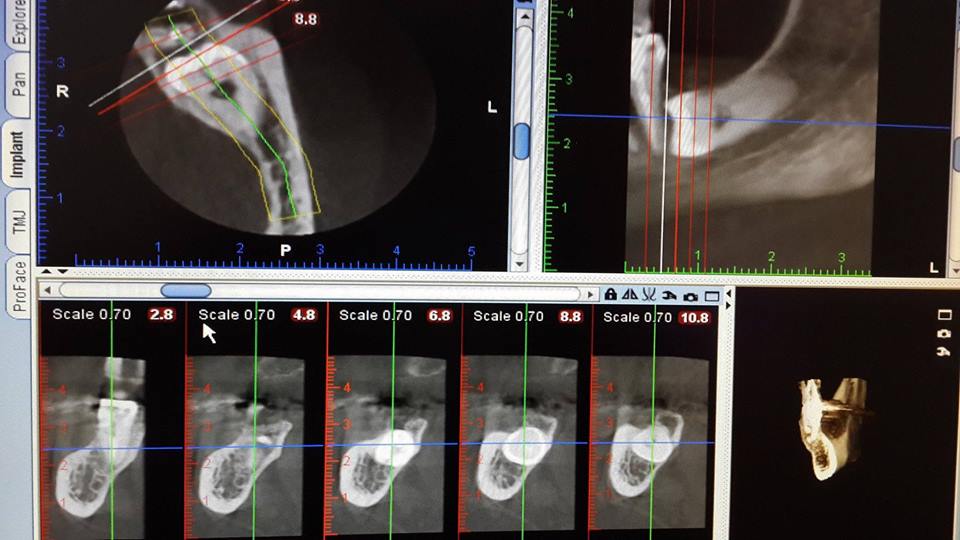

Complex extraction of wisdom tooth

The patient was removed from the retinued tooth of wisdom.